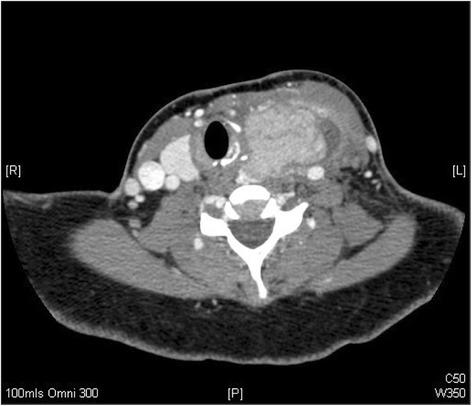

A 29-year old female was found to have a thyroid mass during an antenatal assessment. Following a wound infection from Caesarian section she developed a rapidly progressive thyroid abscess. Incision and drainage of the abscess, and subsequent histology revealed papillary carcinoma. She subsequently underwent both total thyroidectomy with level 6 dissection and radio-iodine ablation post-natally.